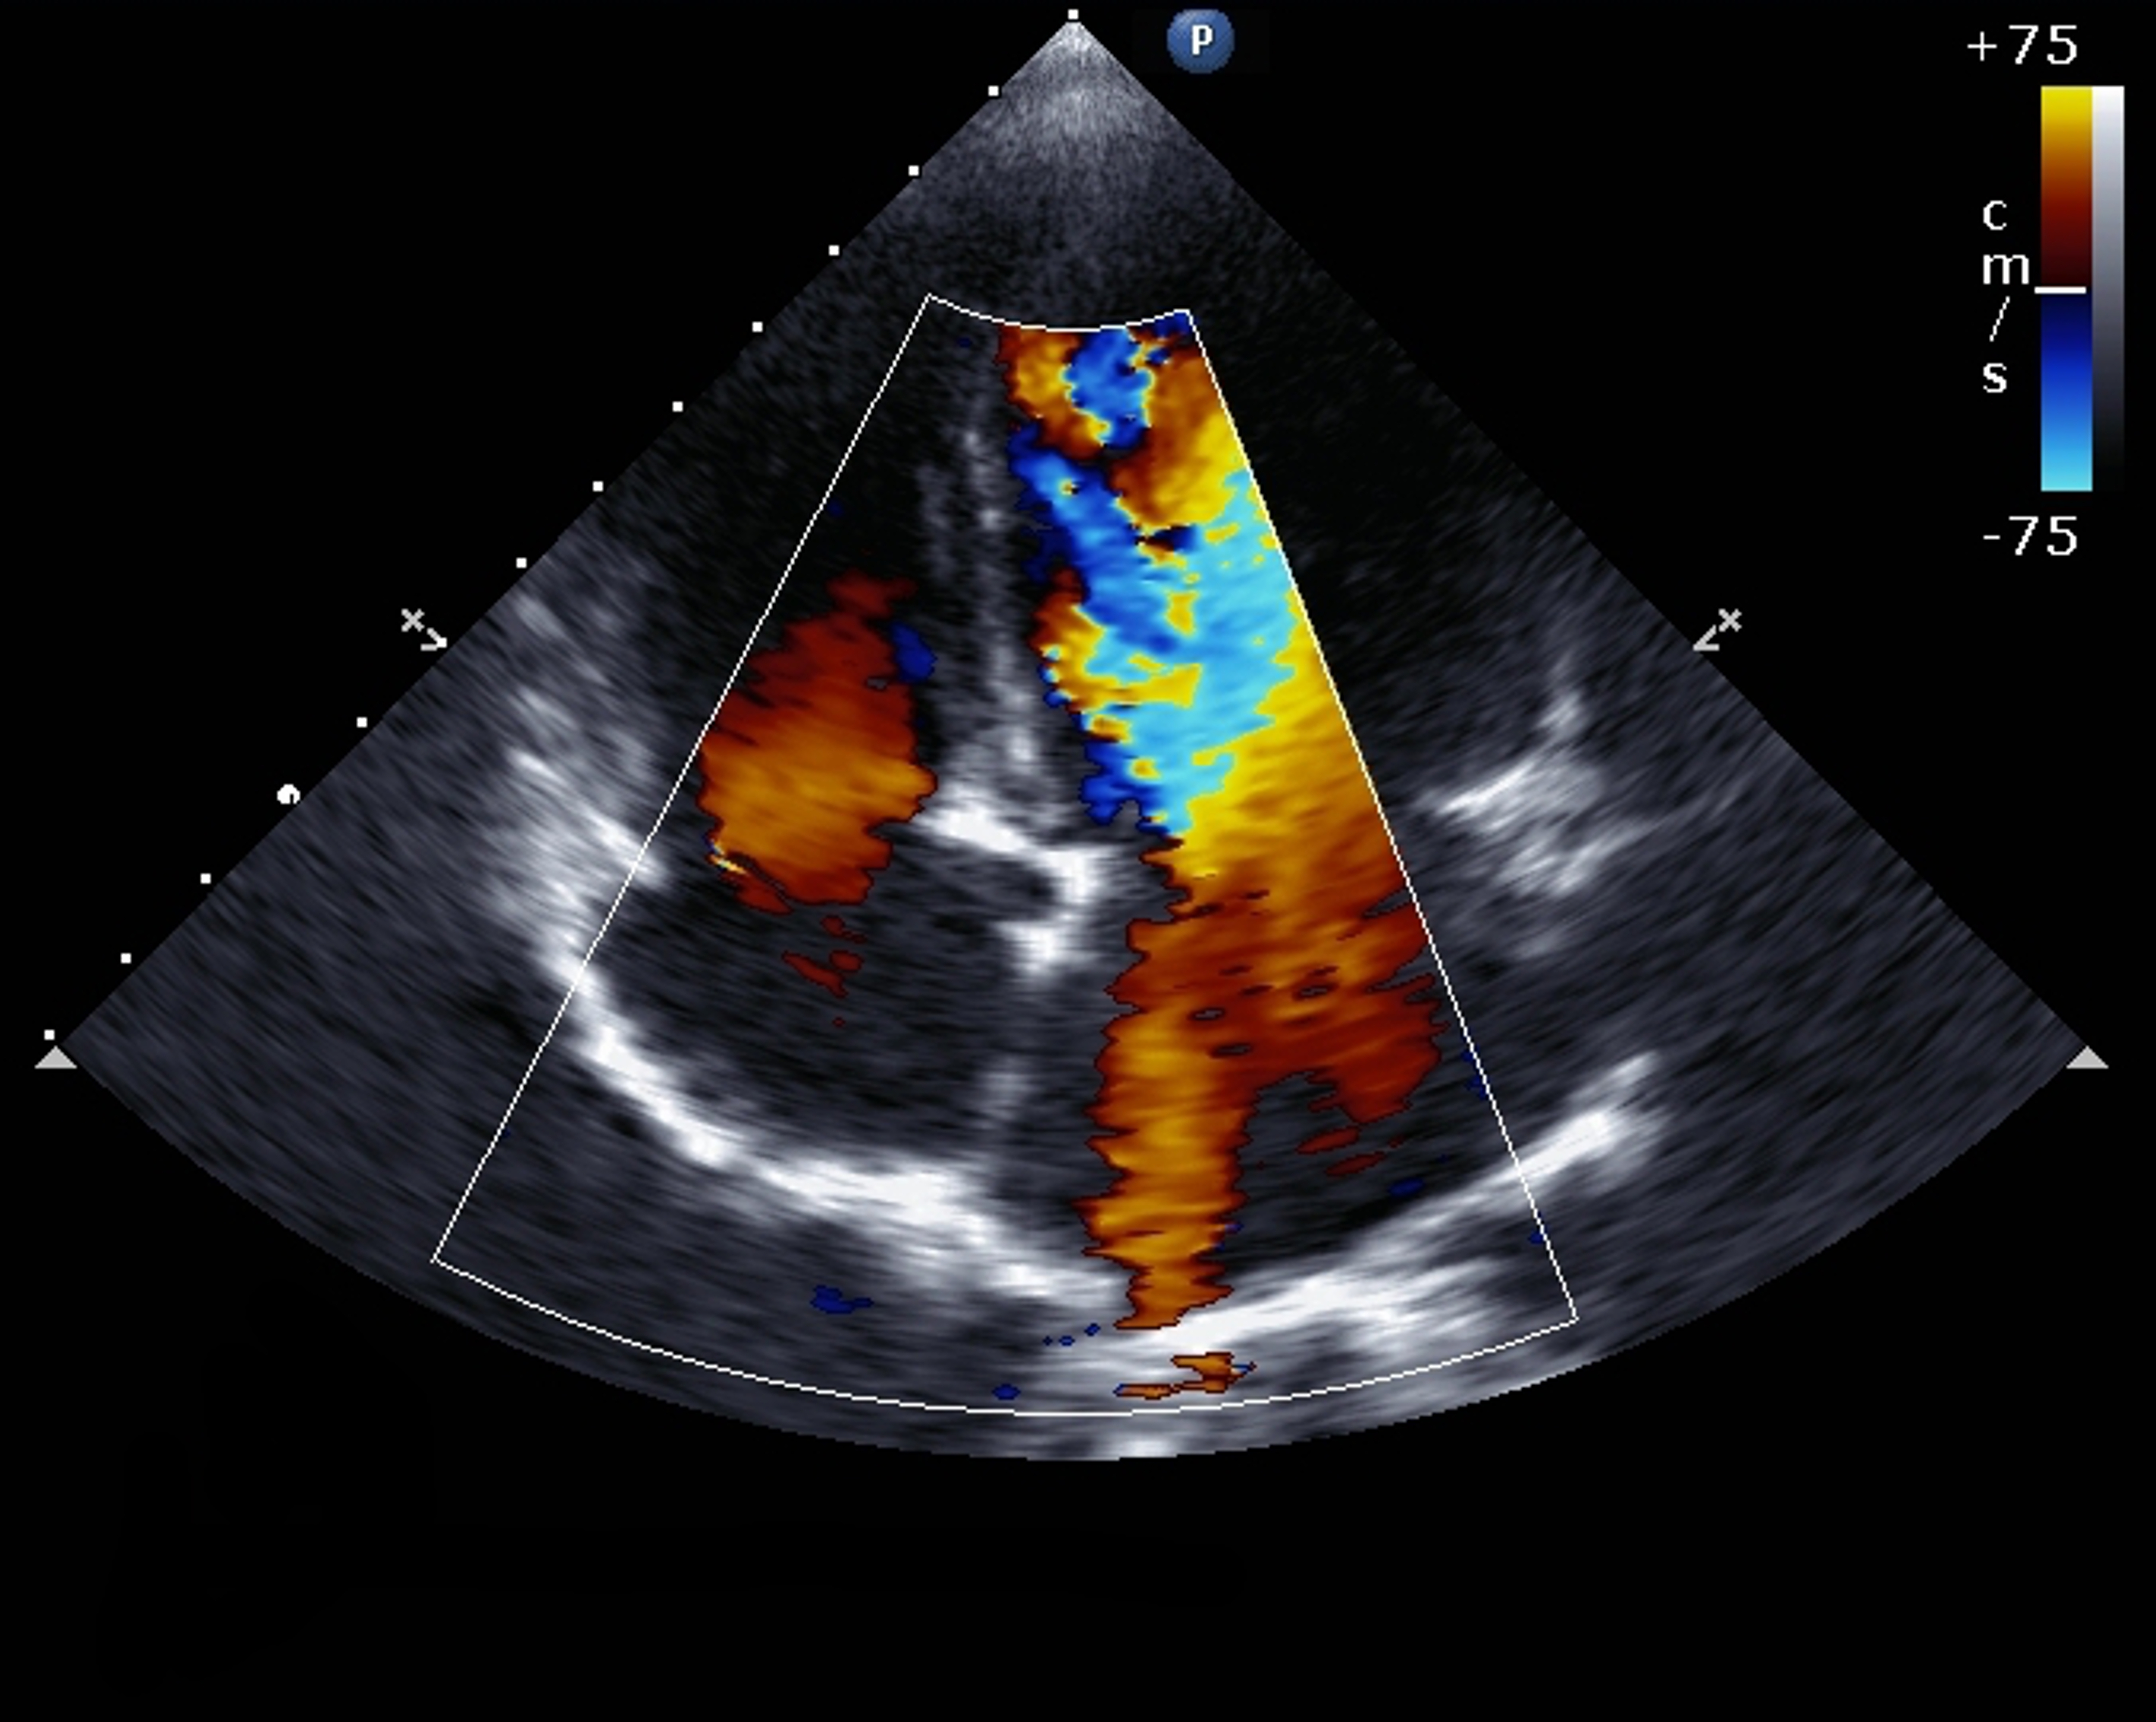

Pulmonary arterial hypertension (PAH) is a rare disease with a poor prognosis if not treated. Pharmacological treatment options for PAH have increased significantly over the past 10 years, with availability of intravenous, oral and inhaled drugs targeting the nitric oxide, endothelin and prostacyclin pathways.

This module includes an evidence-based overview of PAH treatment as applied to clinical practice, focusing on Group 1 and Group 4 PH (for which there is good evidence for pharmacological treatment).